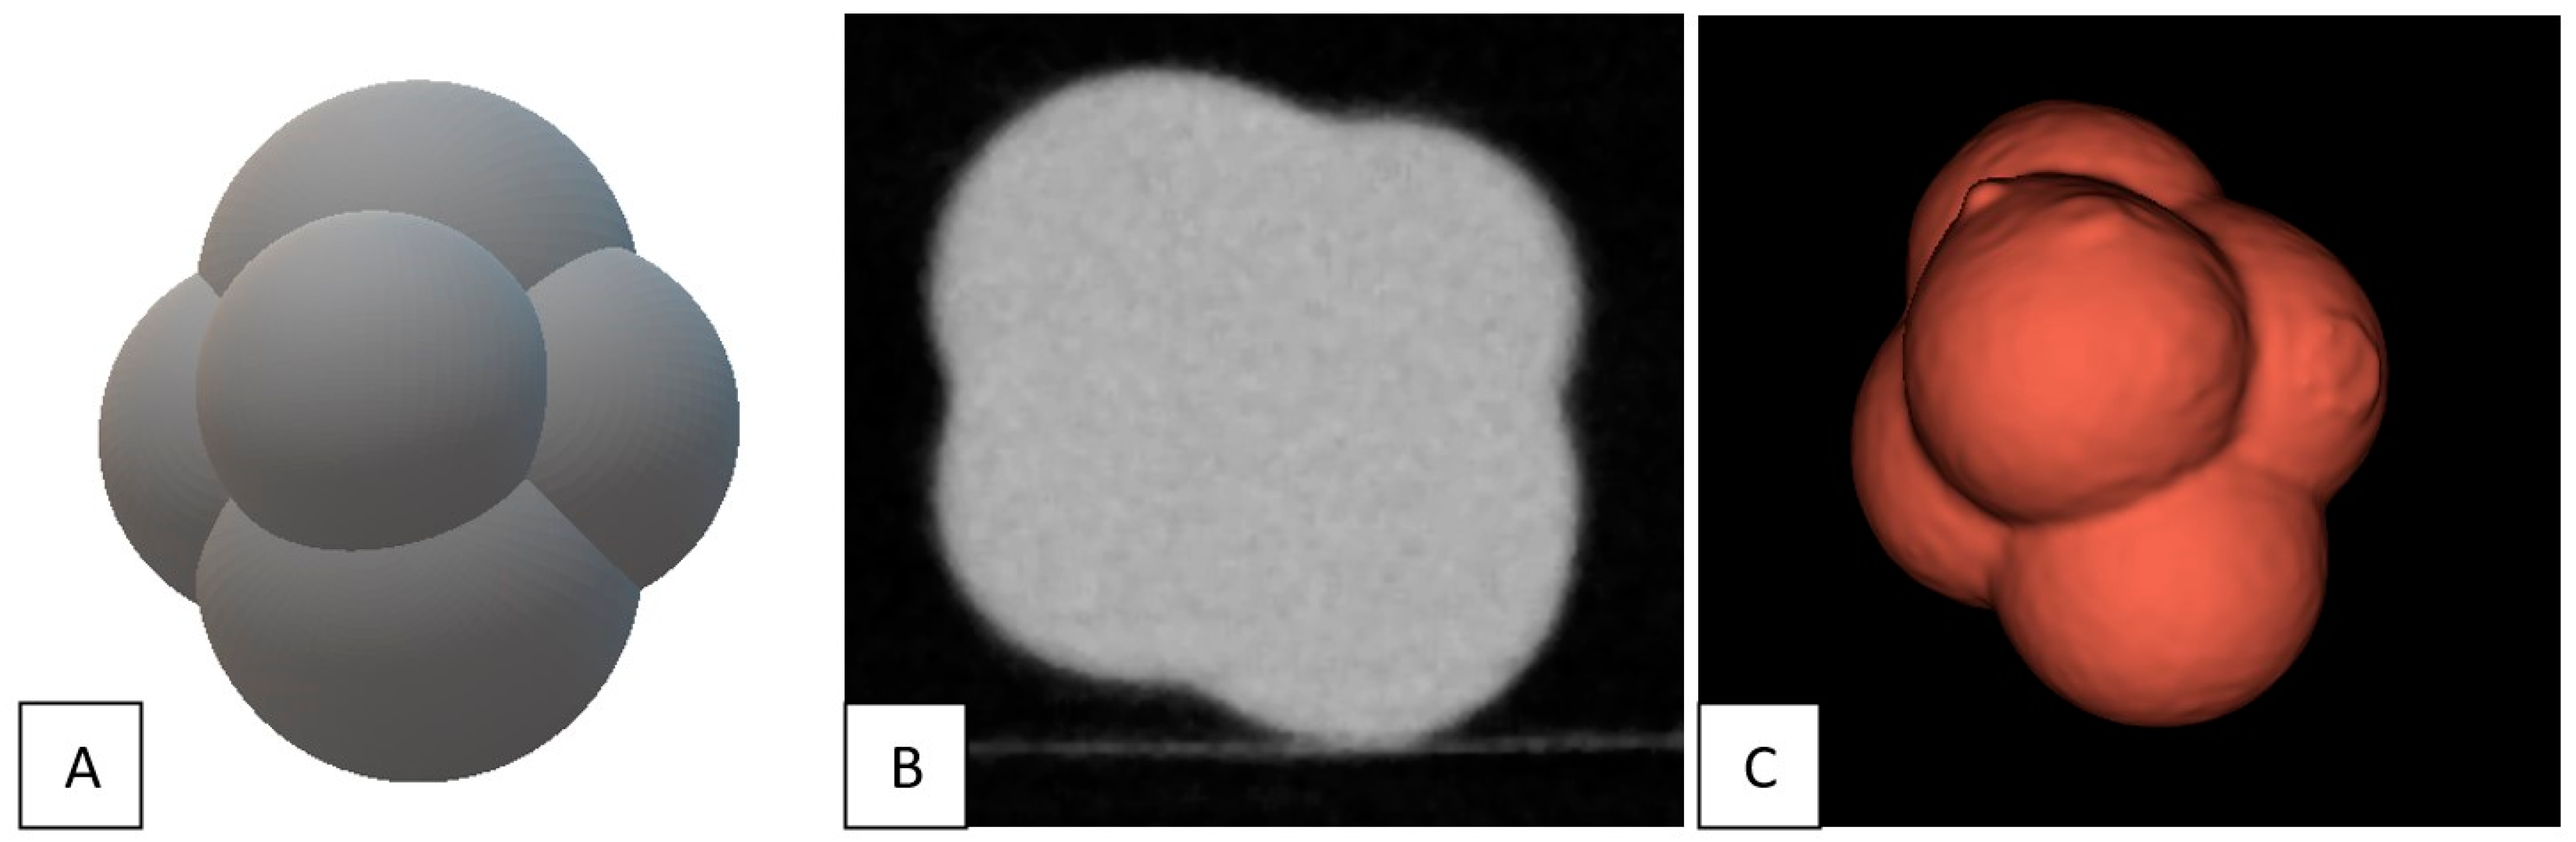

2.1. Phantom and Nodules